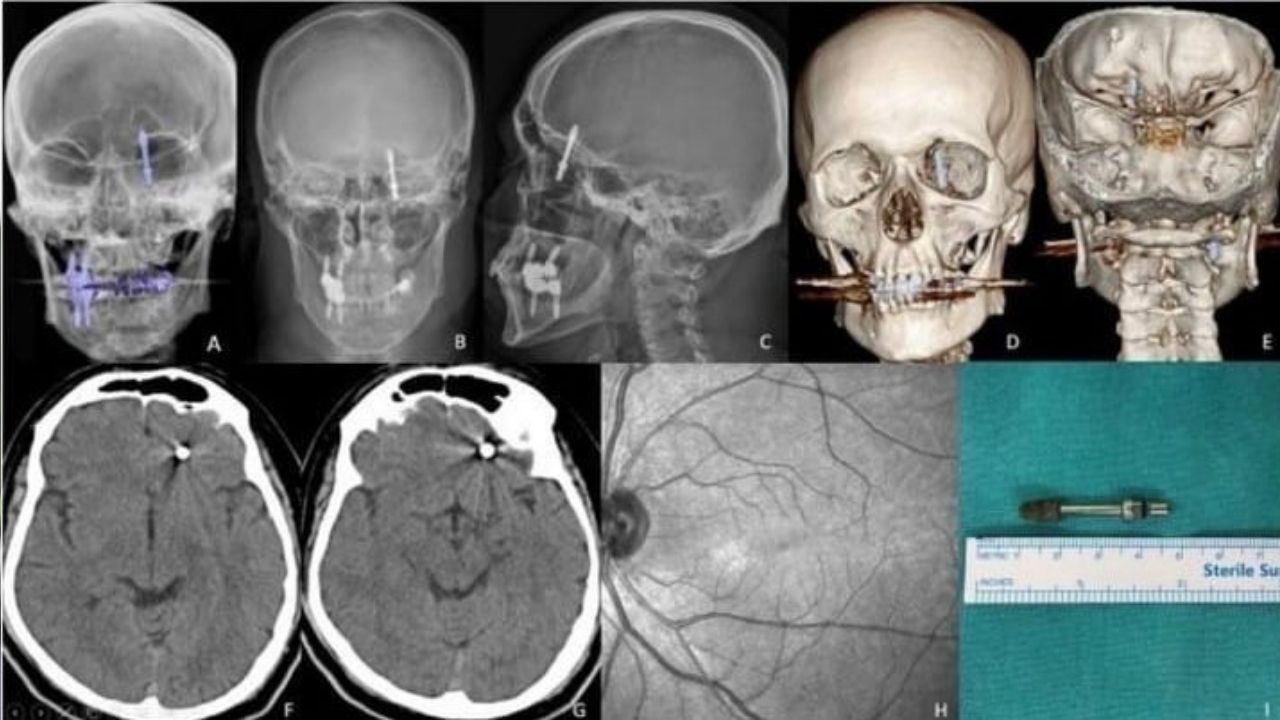

Nilüfer ilçesinde özel bir diş kliniğinde muayene olan Yılmaz'a, dişlerinin sallandığı gerekçesiyle implant tedavisi önerildi. Ancak iddiaya göre, doktor A.D.'nin hatalı müdahalesi sonucu implant vidası çene kemiğini delip kafatasına saplandı.

Baygınlık geçiren Yılmaz, kliniğin kendi aracıyla hastaneye kaldırıldı. Tomografi çekiminde vidanın beynine kadar ilerlediği ortaya çıktı. Acil ameliyata alınan talihsiz adam, saatler süren operasyonla ölümden döndü.